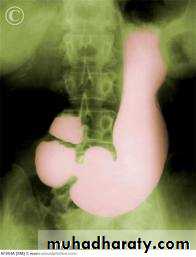

Barium meal Fluoroscopy + spot films Preparation

The Normal Anatomy of Stomach1- Shape.2-Size.3-Site.4-Anatomical parts.5-Mucosal pattern.

Normal Anatomy of DuodenumDuodenal cap.Duodenal loop

Hypertrophic pyloric stenosisCause:A. Congenital typeB. Adult type